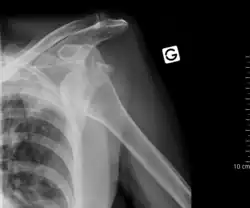

Die Ursache einer traumatischen Luxation ist meist ein indirektes Trauma, beispielsweise ein Sturz auf den Arm oder ein Aufkommen mit dem Bein[2] bei einem Sprung. Am häufigsten ist die Schulterluxation, die mehr als 50 % aller traumatischen Luxationen ausmacht, gefolgt von der Ellenbogenluxation. Auch Luxationen am Knie oder Sprunggelenk treten häufig auf.[3] Fast alle Gelenke können betroffen sein (auch Kieferluxation). An den Fingergelenken führen meist Überstreckverletzungen zur Luxation, häufiger beim Handball und Volleyball. Die Schultereckgelenk-Luxation entsteht am häufigsten beim Fahrradsturz (s. Bild). Selten kann auch direkter Zug eine Luxation auslösen, wie bei der kindlichen Radiuskopfluxation durch Zug am gestreckten pronierten Arm (Pronatio dolorosa Chassaignac).

Beweisend sind Röntgenaufnahmen in zwei Ebenen, wobei seltene Formen (wie die hintere Schulterluxation) und kindliche Luxationen auch dabei schwer zu erkennen sind. Dann hilft eine Computertomografie (CT), Kernspintomographie (MRT) oder Arthrografie (besondere Röntgentechnik mit Einbringen eines Kontrastmittels in das Gelenk). Bei Kindern sind Luxationen im Ultraschall gut darstellbar.